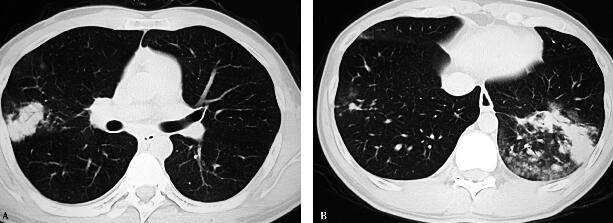

治疗三天后,患者体温不下降,仍持续在38~39℃;咳嗽加重,出现咳黄痰;肺部听诊出现左下肺湿啰音;胸部CT(6月26日)提示感染面积扩大(图2A右肺中叶斑片影,B左肺下叶斑片影);实验室检查示支原体抗体(IgM)>1∶320;痰培养:肺炎链球菌生长。

图2